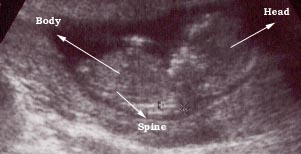

Photo One

6 weeks fetus

This a six week pregnancy and a transvaginal probe was used.